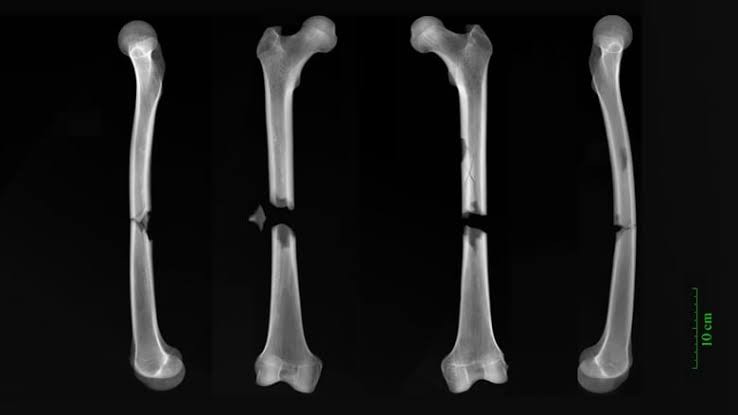

وكشف تحليل بالأشعة السينية للعظام عن مستويات متفاوتة من المشقة عبر الطيف الاجتماعي، ومنها الحوادث، أو إصابات مهنية، أو العنف.

ومع ذلك، رُصدت الإصابة الأشد خطورة لراهب أصيب بكسور كاملة في منتصف عظم الفخذين، بينما عُثر على إصابات الهيكل العظمي المرتبطة بالعنف لدى حوالي 4% من السكان.